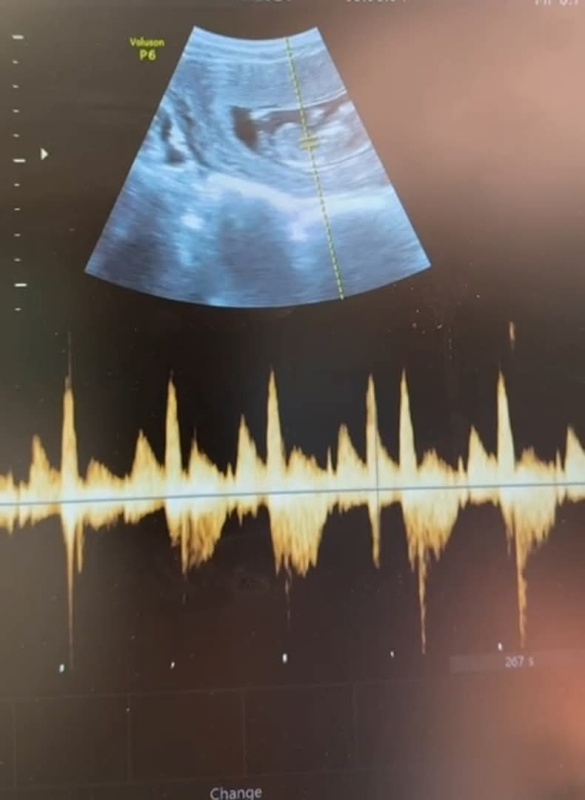

Intervenția a decurs favorabil, iar momentul cel mai încărcat emoțional a venit la ecografia postoperatorie: bătăile inimii fetale erau prezente.

Un detaliu mic ca dimensiune, dar uriaș ca semnificație pentru toți cei implicați.